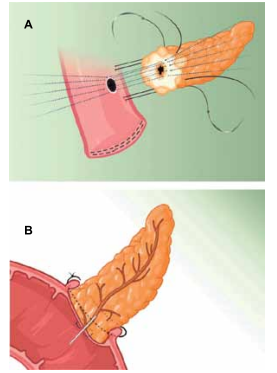

A imagem a seguir apresenta dois tipos de anastomose

pancreatojejunal comumente utilizadas após duodenopancreatectomia, procedimento padrão no tratamento de

tumores periampulares.

(Arquivo pessoal; imagens usadas com autorização)

Com base nas imagens e nos conhecimentos atuais, é correto afirmar que

(Arquivo pessoal; imagens usadas com autorização)

Com base nas imagens e nos conhecimentos atuais, é correto afirmar que